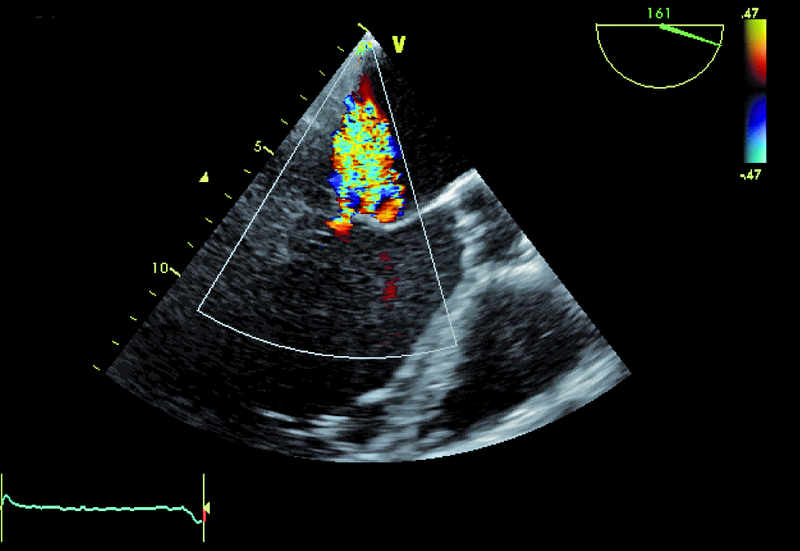

Niedomykalność zastawki mitralnej o etiologii niedokrwiennej pogarsza rokowanie u chorego z chorobą wieńcową i istotnie obniża komfort życia. Fala zwrotna w prezentowanym materiale sięga ujścia żył płucnych (ryc. 1), a ciśnienie w jamie prawej komory jest podwyższone (ryc. 2). U chorych, u których nie ma wskazań do rewaskularyzacji lub u chorych z chorobami współistniejącymi poszukuje się innych metod interwencji poza chirurgiczną naprawą. Punktem wyjścia dla rozważań o możliwości leczenia niechirurgicznego jest dokładna ocena anatomii zastawki. Wykorzystuje się dane zarówno z badania przezklatkowego, jak i przezprzełykowego, choć oczywiście optymalnym rozwiązaniem byłoby zastosowanie obrazowania trójwymiarowego. Sporo uwagi poświęca się ostatnio naprawie płatków zastawki za pomocą tzw. urządzenia mitraclip. Techniką tą można interesować się zwłaszcza w kontekście chorych bez istotnego poszerzenia pierścienia zastawki (w prezentowanym przypadku średnica pierścienia nie przekraczała 35 mm), a z dostatecznie dużą ilością tkanki tworzącej jej płatki. Założeniem techniki mitraclip, przypominającej zabieg chirurgiczny Alfieriego, jest połączenie segmentów środkowych płatka przedniego i tylnego. Skutecznie wykonany zabieg poprawia koaptację płatków i zapoczątkowuje odwrotny remodeling lewej komory, zmniejszający z kolei udział tzw. sił pociągających. Na co trzeba zwrócić uwagę, oceniając pacjenta z niedomykalnością mitralną, towarzyszącą chorobie niedokrwiennej? Niedomykalność (wg podziału Carpentiera typ 3b) powinna rzeczywiście powstawać między segmentami A2 a P2 (ryc. 3), ponieważ tylko w takim wypadku połączenie płatków i wytworzenie dwóch osobnych ujść może choremu przynieść korzyść. Ważnym elementem oceny jest uzyskanie projekcji przezżołądkowej poprzecznej. Ta projekcja bardzo dobrze ilustruje wielkość płatków i ich wzajemną relację (ryc. 4 – większy płatek tylny znajduje się bliżej głowicy). Przeciwwskazaniami do zabiegu implantacji mitraclip może być nadmierna grubość płatków, utrudniająca ich uchwycenie przez ramiona urządzenia, mniejsza niż 2 mm długość koaptacji oraz większa niż 11 mm głębokość koaptacji w stosunku do linii podstawnej pierścienia zastawki. Wymienionych cech nie potwierdzono w badaniu (ryc. 5, 6) i zakwalifikowano chorego do zabiegu w trybie planowym. Warto pamiętać, że echokardiografia służy nie tylko ocenie wskazań do zabiegu, ale stanowi także podstawę jego monitorowania.